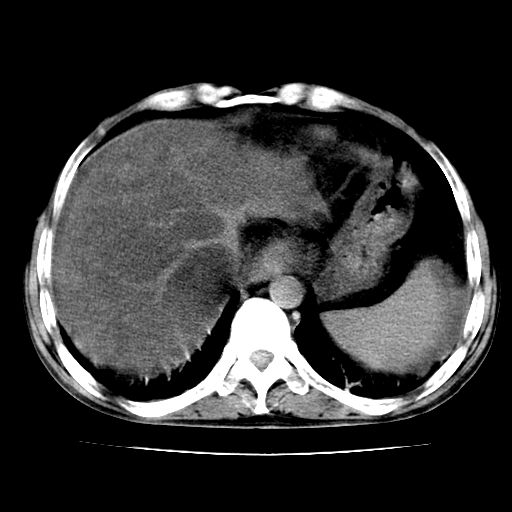

男,55岁,发现“肝硬化”5年,现腰疼、腹胀10余日,巩膜黄染、腹稍胀,肝肋下3指,质硬无压疼,移动性+,血生化:总胆、直胆、间胆均升高。

g1:肝硬化、脾大、腹水。

2:脂肪肝。

3:弥漫性肝癌待排。